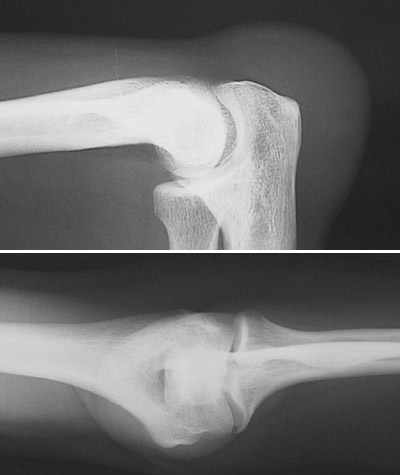

There is soft tissue swelling around the elbow in this radiograph. This is the result of bursitis. Repetitive motion may irritate the joint and surrounding soft tissues, leading to fluid collection into bursal sacs, here the olecranon bursa (another name for the process at this site is "tennis elbow"). There is pain and swelling on physical examination. If chronic, there can be hemorrhage and calcification with chronic inflammation and fibrosis.